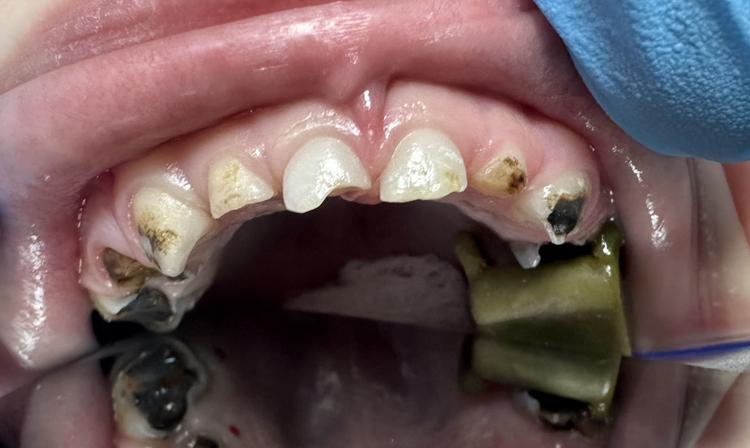

ПРИМЕРЫ РАБОТ

Специалист в области диагностики и лечения кариеса и его осложнений молочных и постоянных зубов у детей, удаления молочных зубов и профессиональной гигиены полости рта у детей.

В совершенстве владеет методикой восстановления и протезирования коронками молочных зубов.